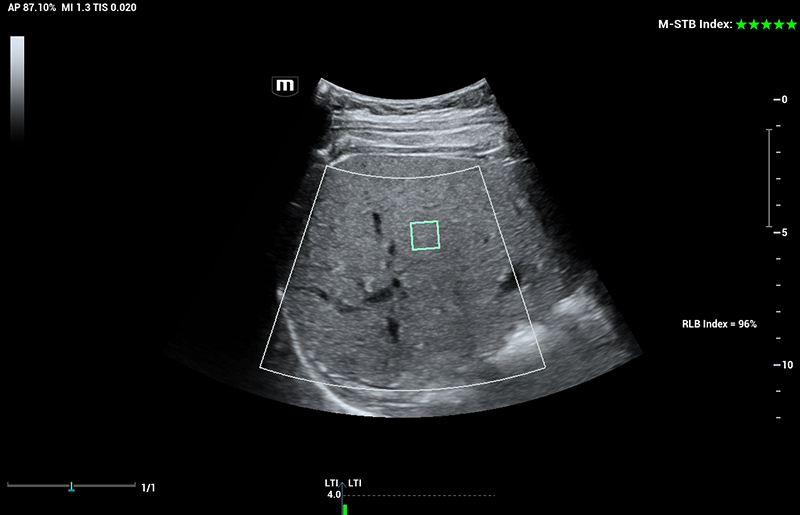

Für die Ultraschalltechnologie stellt die ZST+-Plattform einen bedeutenden Fortschritt dar, da sie statt der herkömmlichen Strahlformung die Kanaldatenverarbeitung verwendet. Diese bahnbrechende Innovation löst übliche Zielkonflikte zwischen räumlicher Auflösung, zeitlicher Auflösung und Homogenität des Gewebes auf, woraus sich eine beispiellose Bildqualität ergibt, die den Weg frei macht für unendlich viele Bildgebungslösungen.

Das Resona I9 weist umfassende klinische Lösungen für spezielle Anwendungen auf. Auf der Grundlage gründlicher Analysen verschiedener klinischer Szenarien liefert es Innovationen, die den Benutzenden herausragende Klarheit, außergewöhnliche Intelligenz und eine erhöhte Diagnosesicherheit bieten.